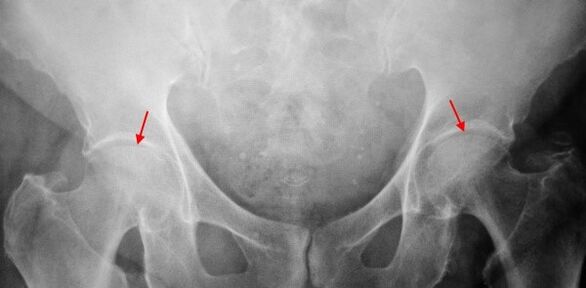

Sui raggi X del paziente, che soffrono del 1,1 ° grado, vengono determinati cambiamenti lievi: un moderato restringimento irregolare della colonna articolare e una crescita ossea attorno al bordo esterno o interno dell'acetabolo senza cambiamenti dalla testa e dal collo della coscia.

Nelle immagini di radiazioni X per la coxartrite del 2 ° grado, viene determinato un significativo restringimento del divario comune (più della metà dell'altezza normale). La testa della coscia è leggermente spostata, deformata e aumentata e i suoi contorni diventano irregolari. La crescita ossea con questo grado di coxartrosi si verifica non solo all'interno, ma anche sul bordo esterno dell'acetabolo e va fuori dalla cartilagine.

Nel caso di raggi X per la coxartrite del 3 ° grado, è dimostrato un forte restringimento della colonna articolare, un'espansione pronunciata della testa della coscia e diverse crescita ossea.

La diagnosi di coxartrosi si basa su segni clinici e dati di ulteriori studi che sono radiografici. In molti casi, i raggi X consentono non solo il grado di coxartrosi, ma anche la causa del suo aspetto. Ad esempio, le scene e l'appiattimento dell'acetabolo indicano un aumento dell'angolo diafisico del collo e la forma della parte prossimale del femore sono indicati che la rosa di Coksart è una conseguenza della malattia o dell'epifisissis giovanile di Pertes. Nel caso di raggi X di pazienti con coxartrosi, è possibile determinare cambiamenti che indicano lesioni.